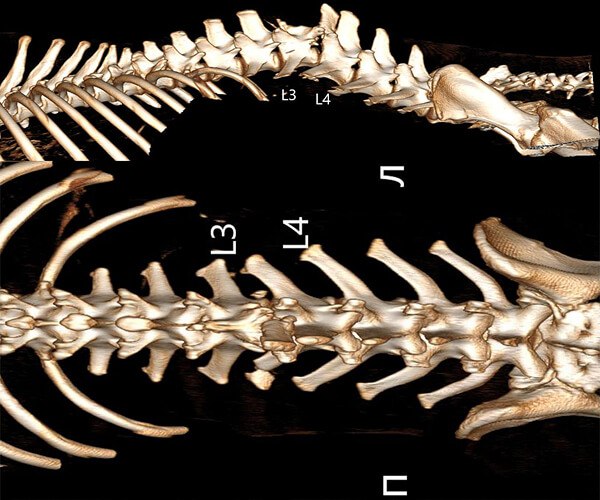

Сейчас в теле щенка застряли пули, повреждён позвоночник и спинной мозг. Он не может лечь, ест и спит только сидя, и каждую минуту терпит боль. Каждая попытка движения, каждый вдох даются ему с трудом. Постоянная боль истощает его силы, лишая надежды. Врачи борются за его жизнь, но состояние Зухрая критическое. Необходимы экстренные меры, чтобы стабилизировать его состояние и предотвратить дальнейшее ухудшение.

Врачи говорят, что полностью восстановить чувствительность уже не получится. Но у Зухрая есть шанс облегчить страдания и прожить жизнь без постоянной боли. Для этого нужны обследования и лечение в Москве. Специализированная клиника в столице располагает необходимым оборудованием и опытными специалистами, которые смогут оказать ему квалифицированную помощь. Каждое обследование, каждая процедура – это шаг к облегчению его страданий, к возможности дышать полной грудью, к возвращению к жизни, пусть и с ограничениями.